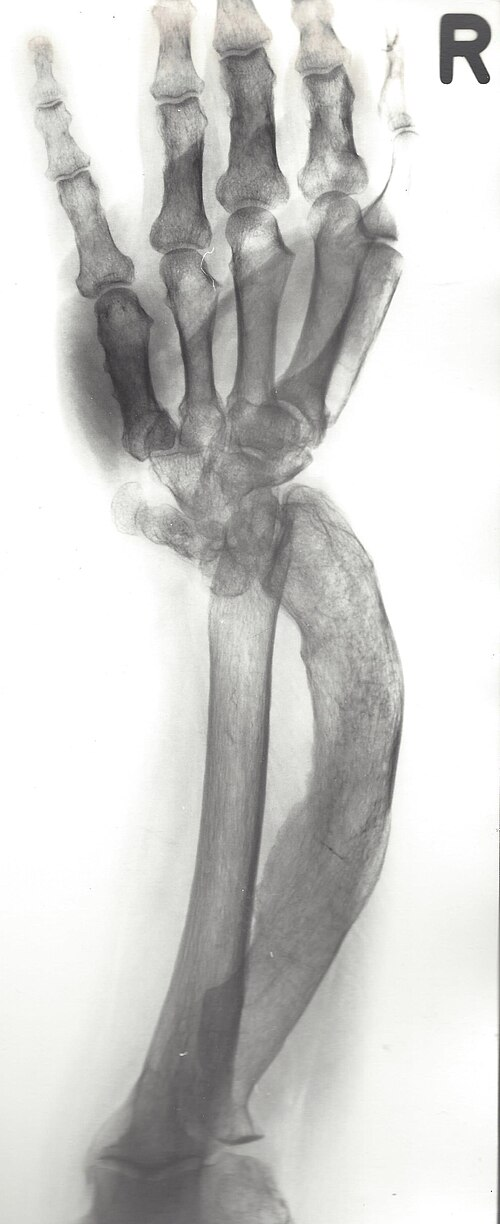

Madelung’s deformitet er en tilstand i håndleddet som kjennetegnes av en forkortet distal radius med volar-ulnar kurvatur og en dorsalt prominent distal ulna¹. Tilstanden kan være medfødt (flere osteokondromer)² eller ervervet som følge av traume mot vekstplaten (traumatisk tidlig lukking av epifysen eller Salter-Harris fraktur type V)³.

Viktige funn på røntgen:

Økt dorsal og radial konveksitet i distal radius

Økt volar og ulnar tilt i den distale radius-leddflaten

Bredere interosseøs spalte

Relativ dorsal posisjon av ulnahodet

Pyramideformet karpus¹⁹